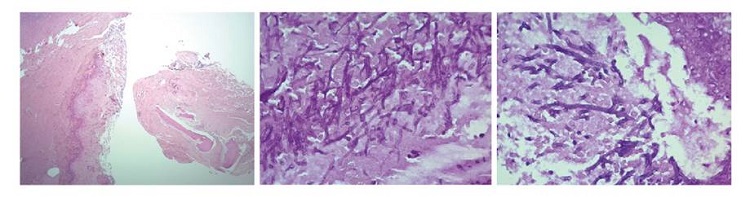

En el examen directo con KOH al 10 % de las muestras de tejido de los senos paranasales, fue posible observar hifas no tabicadas sugestivas de zigomycetos, y en los cultivos en agar Sabouraud incubados a 26 °C se obtuvo crecimiento mixto de dos hongos filamentosos hialinos (figura 3) que fueron identificados por técnica proteómica con el equipo MALDI- TOF MS como Aspergillus flavus/oryzae y Rhizopus oryzae complex. Estas estructuras fúngicas también se describieron en las biopsias con tinción de PAS y Gomori-Grocott (figura 4).

En el estudio histopatológico de la infección por mucorales, se observan hifas no tabicadas o paucitabicadas con invasión tisular en las tinciones de hematoxilina y eosina, ácido peryódico de Schiff y Gomori Grocott. A partir del rendimiento descrito del estudio patológico, es conveniente realizar cultivos para la identificación de género y especie 10. Entre los criterios diagnósticos para las infecciones fúngicas invasivas probadas, se encuentra el examen histopatológico, la demostración de infección fúngica en un tejido estéril o la recuperación de estructuras fúngicas en muestras obtenidas en un procedimiento estéril o mediante hemocultivos 6.